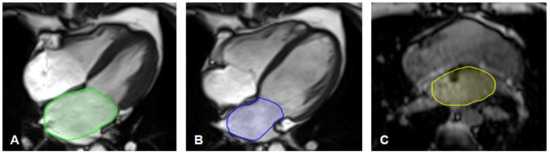

2.4. MR-Image Analysis for Left Atrium Size